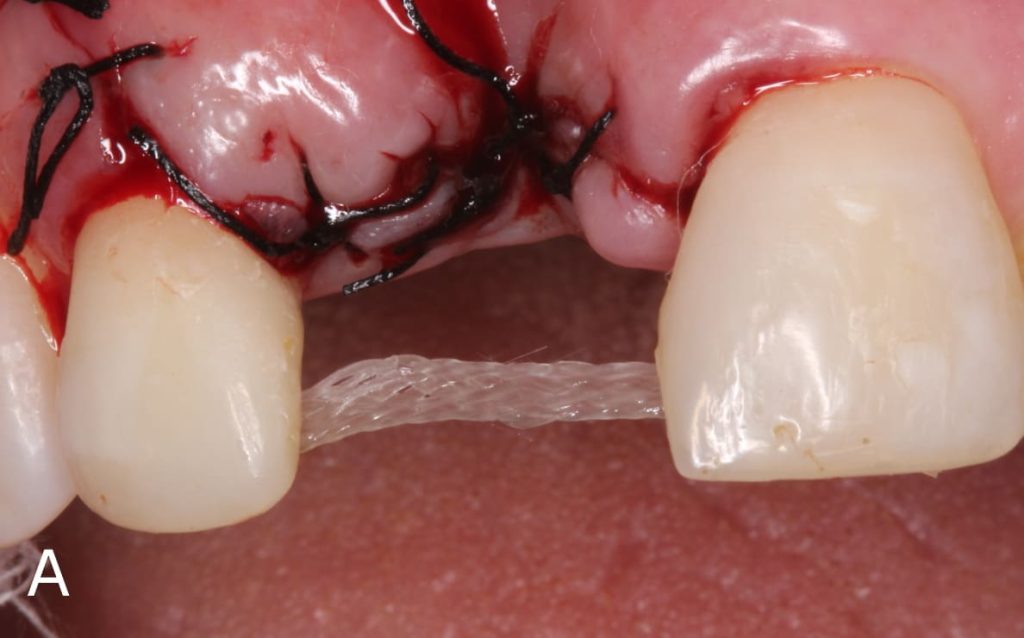

Después de realizar la preparación, grabe con ácido fosfórico al 37% (Angelus Industria de Productos Odontológicos S/A, Paraná, Brasil) durante 30 segundos (Figura 2A), lavar por el mismo tempo y luego secar com chorro de aire. Luego aplique dos capas de adhesivo (Angelus Industria de Productos Odontológicos S/A, Paraná, Brasil) (Figura 2B) y 2 fotopolimerizar por 30 segundos (Figura 3). Después de hibridar los dientes pilares, realizar la preparación del diente, en este caso se utilizó el diente del propio paciente, realizando un desgaste en la región palatina para que el Interlig tenga espacio suficiente para asentarse sobre este diente, y quede completamente cubierto por la resina compuesta. El Interlig ya es uma fibra silanizada e impregnada, por lo que no requiere ningún tipo de tratamiento previo a su uso, basta com cortarlo al tamaño adecuado (Figura 4). Después de realizar el desgaste, use ácido fosfórico al 37 % y adhesivo en el diente de stock, preparándolo para realizar la adhesiva directa.

Se posicionó la fibra de vidrio en las preparaciones de los dientes 21 y 12 (Figura 5), se cubrió el área com resina y se fotopolimerizó por 20 segundos (Figura 6). Luego, el diente de stock se colocó sobre la fibra trenzada y se unió a ella con resina compuesta (Figura 7). Después de posicionar la confección de la prótesis adhesiva, se realizó el ajuste oclusal necesario respetando los fundamentos de una oclusión estable bilateral.